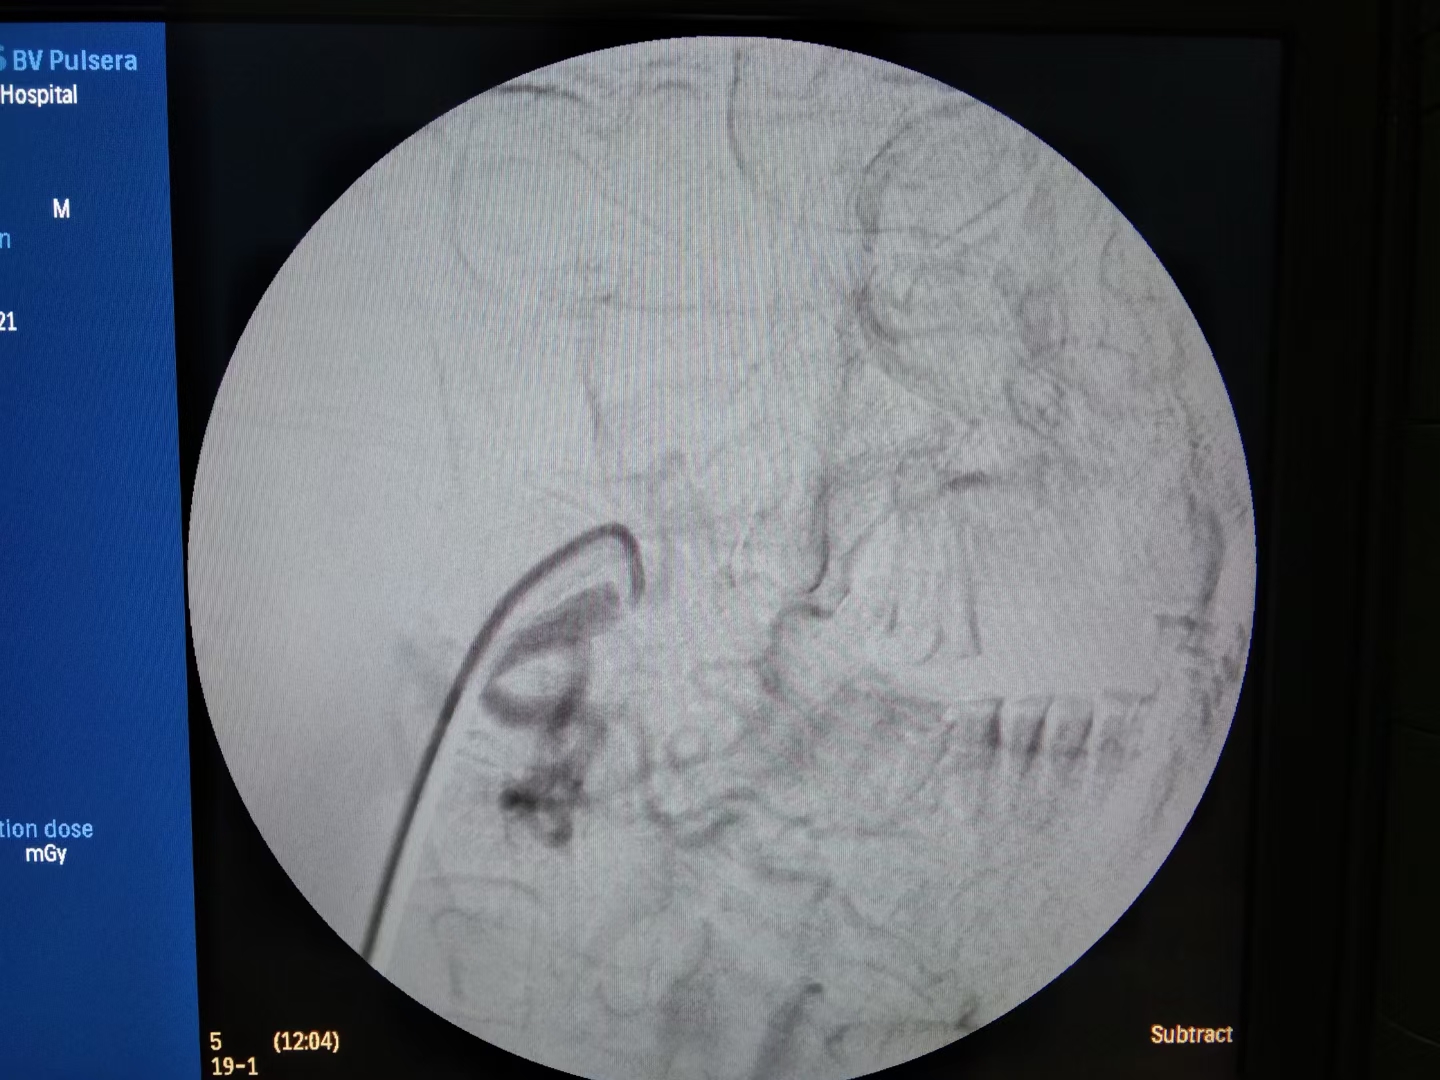

边扩容,输血,止血的同时,推入介入室。消毒、铺巾、穿刺、插管,造影。

术中患者燥动,带来极大风险,一旦误栓颅内动脉,将是灾难性后果。